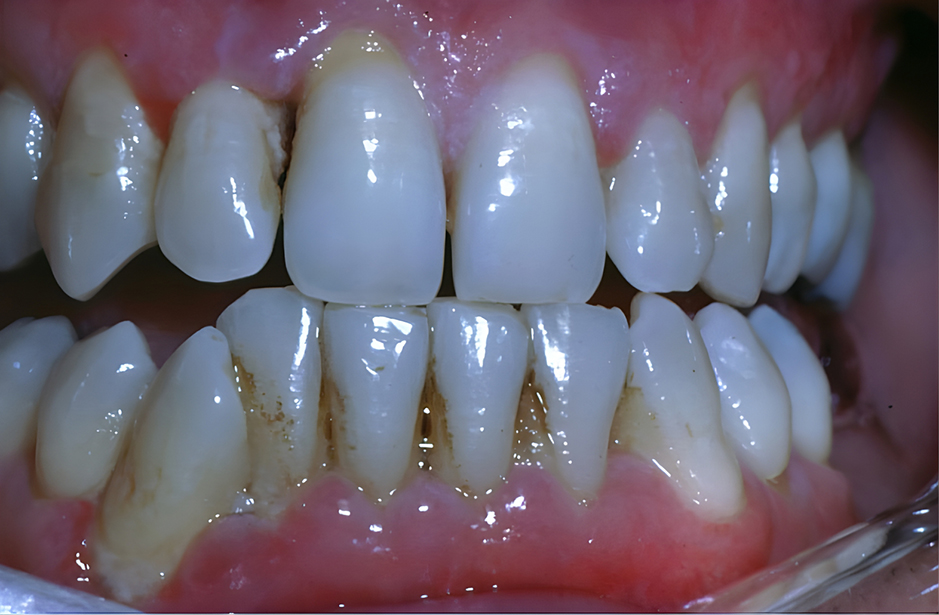

Figure 2: Close-up of teeth and gums shows chronic periodental disease.

Courtesy of Lauren L. Patton, DDS